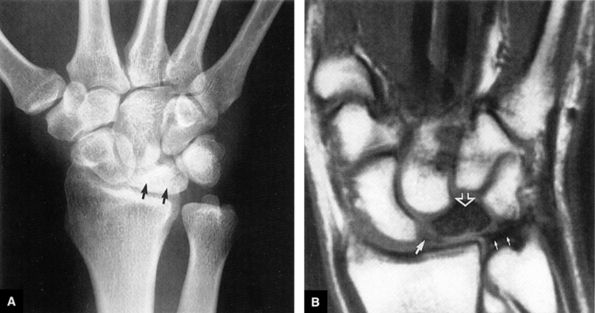

FIGURE 10.1 ● A 3D fast spoiled GRASS (FSPGR) with intra-articular contrast injected into the radiocarpal compartment. The torn lunotriquetral ligament (straight arrow) allows extension of contrast into the midcarpal compartment and the torn radial attachment of the TFC (curved arrow) directs contrast into the distal radioulnar joint. Note the superior trabecular bone detail on this image (coronal image; TR, 40.4 msec; TE, 14.5 msec; FOV, 4 cm; slice thickness, 2.0 mm; matrix, 512 × 256; flip angle, 30°).